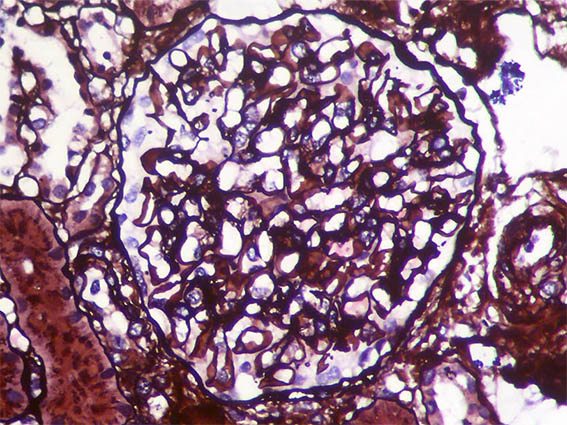

Figure 7. Masson's trichrome stain, X400.